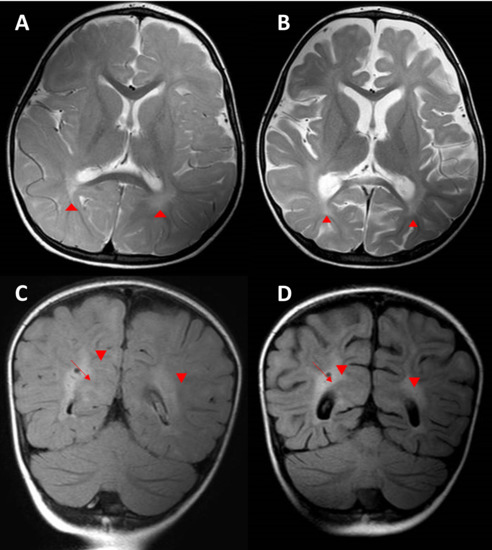

3.4. Development of Neurological Manifestations and MRI Evaluation

At the age of 25 months, she started having gait unsteadiness and neurodevelopmental regression. The neurological manifestations were not suggestive of any specific pattern. A brain MRI was performed and showed prominent subarachnoid space in bifrontal regions, abnormal high signal intensity on T2 and FLAIR in both terminal zones, and incomplete myelination noted on T2 involving U fibers of both peri-sylvian regions and high partial regions (Figure 4A,C). The rest of the workups were inconclusive.

3.5. Development of Respiratory Symptoms and Subsequent Neurological Deterioration

After one week, the patient started to complain of pulmonary issues. She presented to the ER with a cough, respiratory distress, and deteriorated consciousness. The patient required admission to the pediatric intensive care unit. Thereafter, she fell into a coma and was intubated secondary to an influenza infection. During her hospital stay, her level of consciousness improved but had worsening neurological deficits after discharge. She had lost her ability to walk and speak and had decreased response to visual and auditory stimuli. She then had seizures and ophthalmoplegia. Regarding worsening neurological function, the brain MRI was repeated and showed progressive loss of brain volume (Figure 4B,D).

Figure 4. Proband axial brain MRI scans. (A) Axial T2 brain MRI showing delayed myelination for the patient’s age with diffuse abnormal high T2 signal intensity seen in the periventricular deep white matter, more prominent in both peri-trigonal regions (arrow heads). There is also prominence of the subarachnoid spaces in both frontal regions. (B) Follow-up axial T2 brain MRI demonstrating progressive brain atrophy with unchanged delayed myelination and diffuse abnormally high T2 signal intensity seen in the periventricular deep white matter, more prominent in both peri-trigonal regions (arrowheads). (C) Coronal FLAIR brain MRI image demonstrating diffuse abnormally high signal intensity in the periventricular deep white matter, more prominent in both peri-trigonal regions (arrow heads) with prominent VR spaces (arrow). (D) Follow-up coronal FLAIR brain MRI demonstrating the progressive brain volume loss with unchanged diffuse abnormally high signal intensity in the periventricular deep white matter, more prominent in both peri-trigonal regions (arrowheads) with prominent VR spaces (arrow).